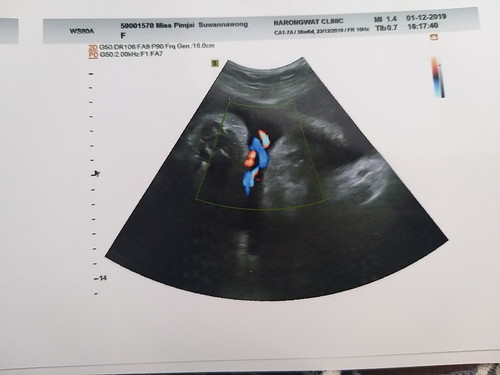

37 W สายรกพันคอ

วันนี้หมอนัดซาวน์ หมอบอกรกพันคอ 1 รอบ แต่โดยส่วนมากจะไม่เป็นอะไร ให้สังเกตุลูกดิ้นดีๆ แต่ก็อดเครียดไม่ได้ คุณแม่คนไหนเคยมีประสบการณ์คล้ายๆกันมาแชร์หน่อยค่ะ ??? กังวลมาก

บ้านนี้เคยเจอค่ะตอน29w. หมอบอกไม่เป็นอะรัยแต่ก็อดกังวลไม่ได้ค่ะถึงกับกินข้าวไม่ลงเลยพยายามไม่คิดมากคอยนับลูกดิ้นก็หายกังวลค่ะตอนนี้น้องคลอดออกมาได้7เดือนแล้วค่ะแม่ไม่ต้องกังวลนะใกล้คลอดแล้วคอยนับลูกดิ้นไว้นะค่ะ

36 วีคคะ วันนี้ไปตรวจคุณหมอบอกสายรกพันคอ1 รอบเช่นกัน